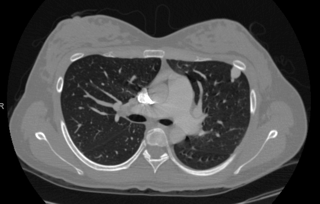

A chest CT scan may also be performed to evaluate for PAVMs. It is also highly sensitive for detection of pulmonary AVMs, but it involves radiation exposure. For this reason, a chest CT is usually reserved for those patients with known PAVMs or a positive echocardiogram with bubble study to determine if treatment is necessary and to determine the anatomy of the AVM and treatment options.

Chest CT depicting

Pulmonary Arteriovenous Malformations (PAVMs).